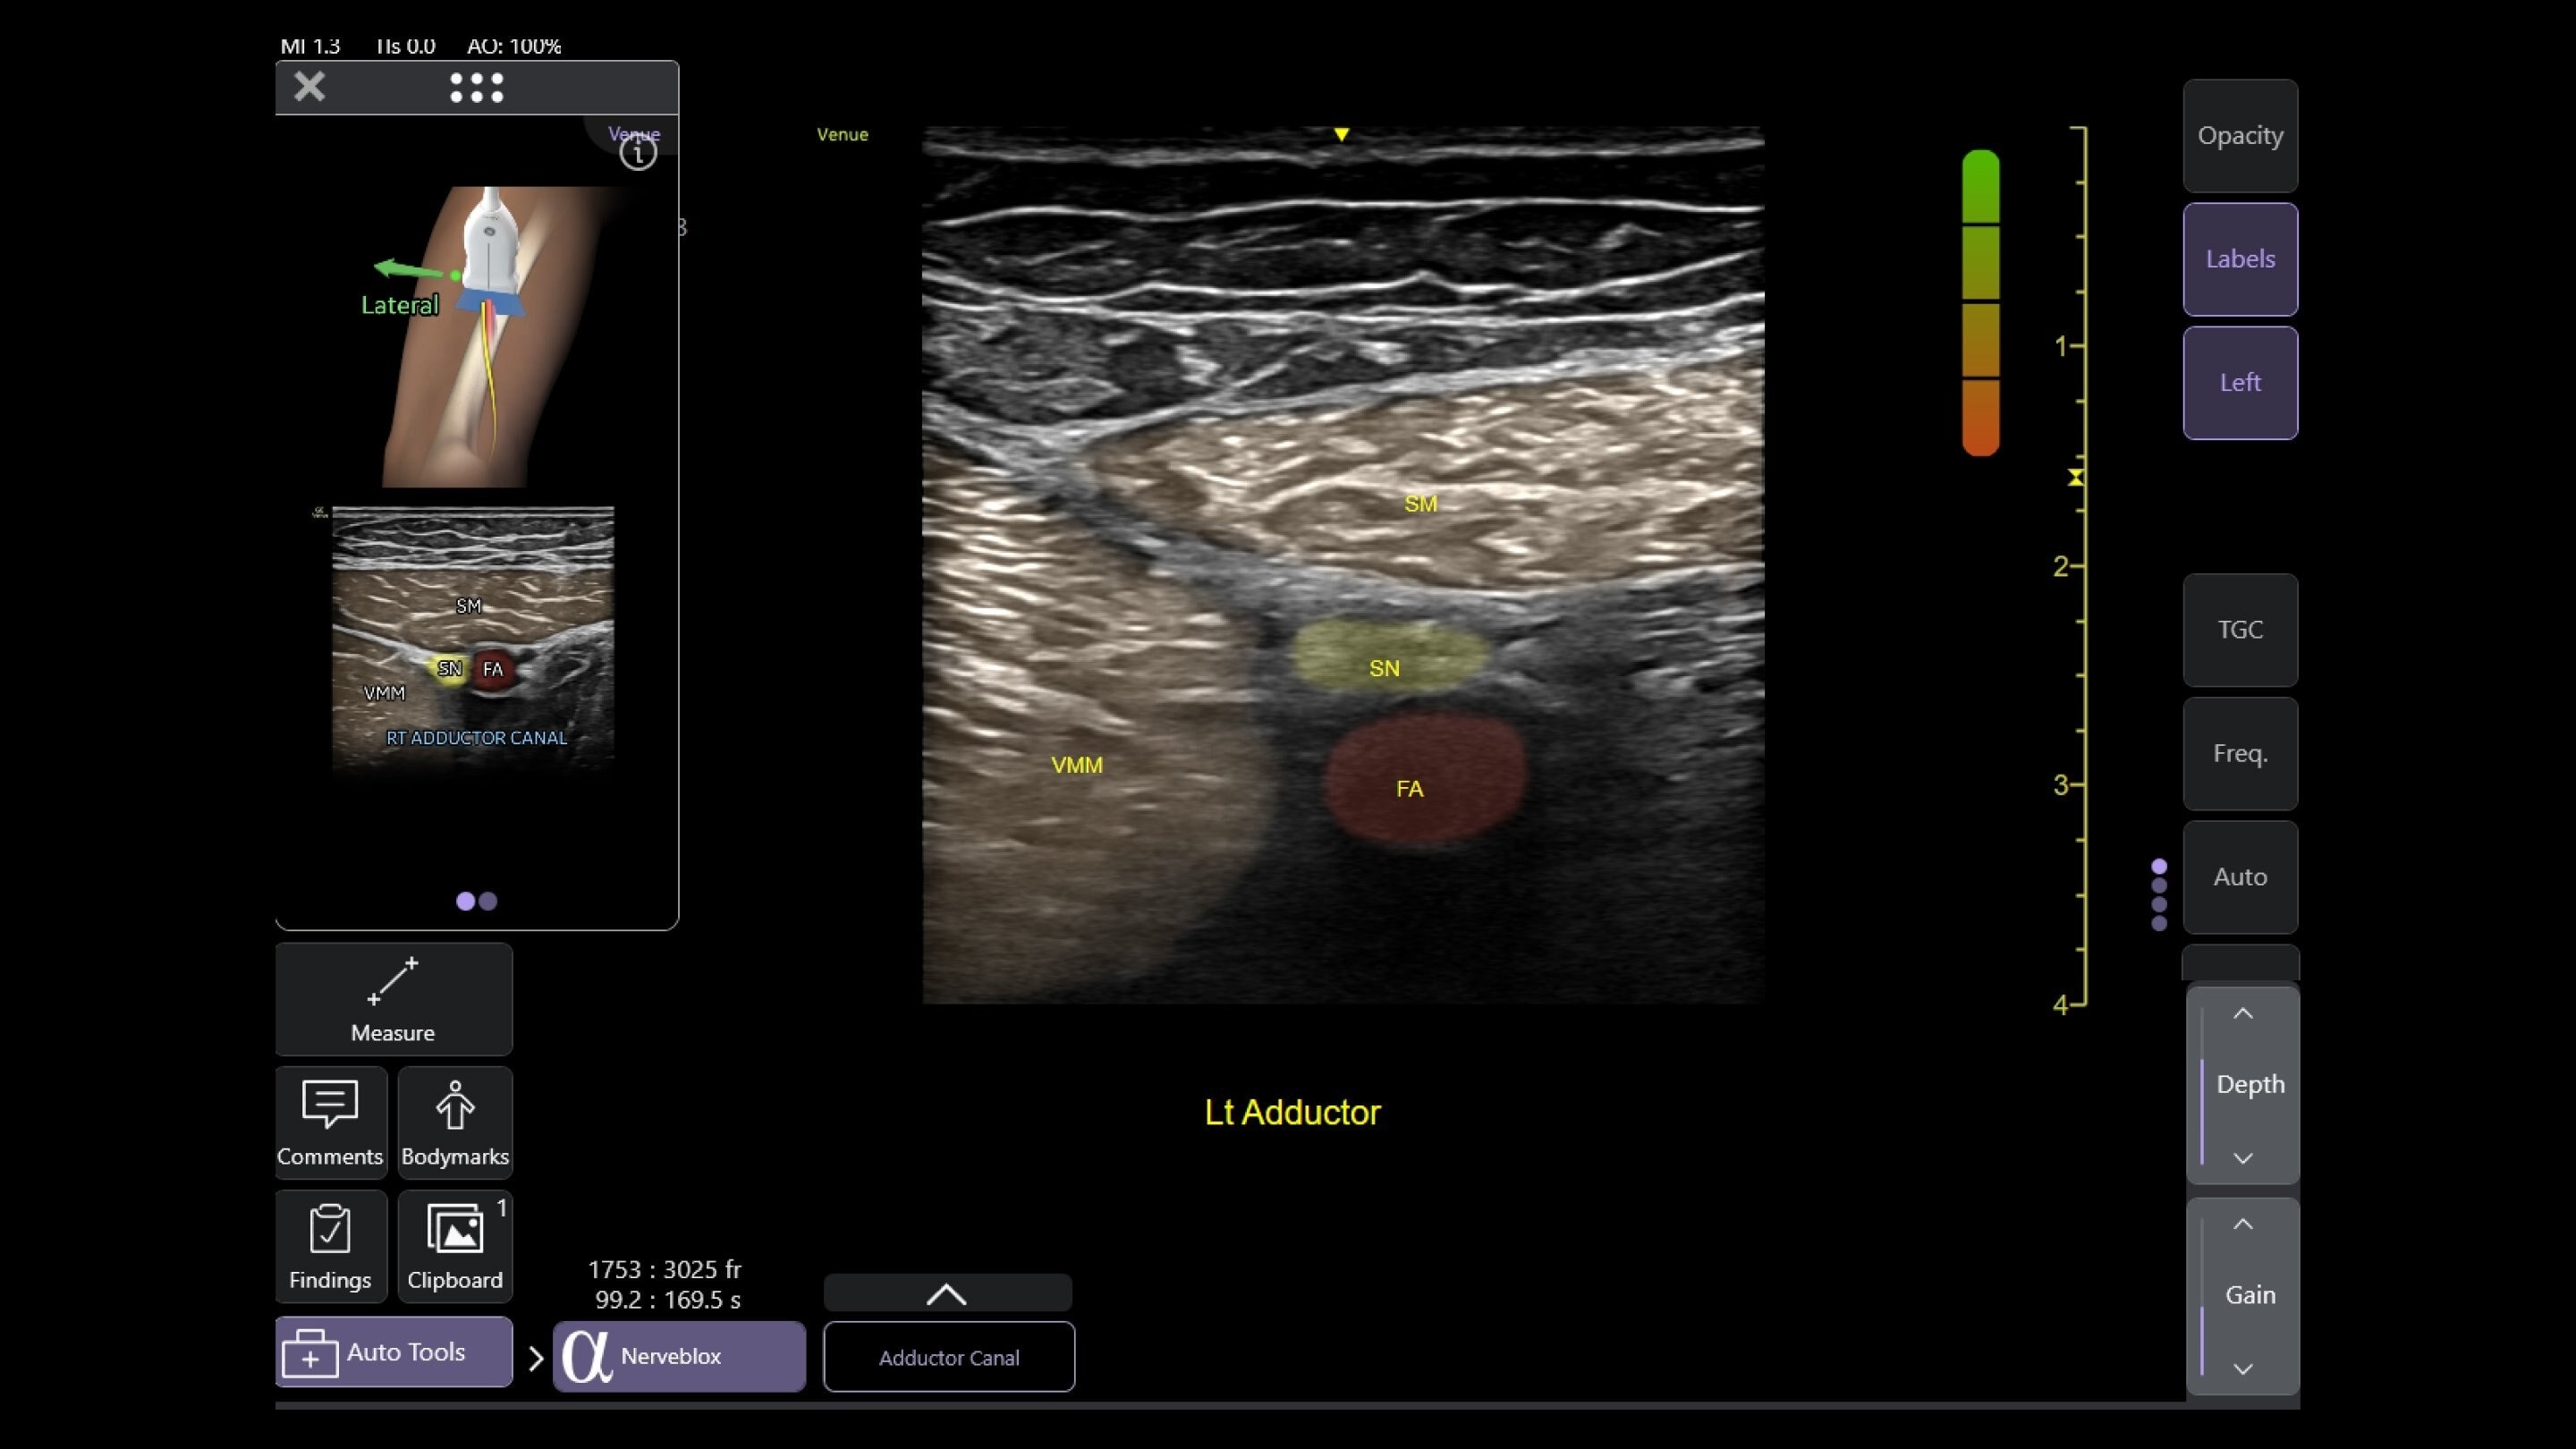

Musculoskeletal (MSK)

A curved array on one side and linear array on the other of the dual wireless probe enables clear assessment of deep and shallow anatomy without switching probes.